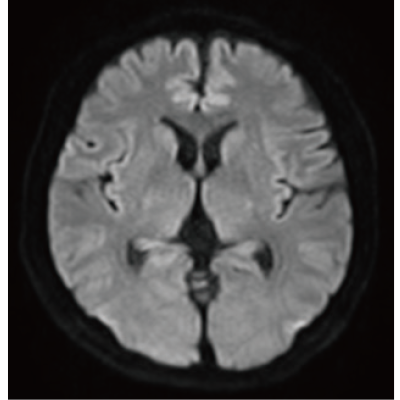

画質を維持しながら撮像時間を短縮するIP-RAPIDと、開発にDeep Learning技術を活用し*8、高画質化を図るDLR Plus。2つの技術の組み合わせにより、診やすい画像を高速で得られます。

IP-RAPID×DLR Plusは撮像時間の短縮も可能なため、同一検査時間であれば、より多くの撮像が可能となります。従来検査に対して、異なる画像種類や断面など、追加撮像によって情報量を増やすことができ、診断をより確かなものに。

IP-RAPID×DLR PlusはVolumeScanやRadialScan、HalfScanといった基本撮像に加え、MultiContrastScanのFatSepやDWIなど多くの撮像法でお使いいただけます。広範囲DWIやWhole Spine撮像など時間のかかるWide Scanにも併用でき、多くの部位で従来よりも詳細な情報を得ることができます。